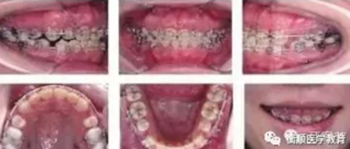

圖4 種植體支抗關(guān)閉拔牙間隙,同時行上頜前、后牙垂直向控制

本病例在減數(shù)4顆第一前磨牙以及4顆智齒后,在治療中充分應用了微螺釘種植體支抗,雙頜后牙區(qū)強支抗確保最大程度內(nèi)收前牙并維持磨牙中性關(guān)系;通過利用上后 牙區(qū)頰腭側(cè)種植釘持續(xù)輕力壓低后牙,減小下頜平面角,使下頜逆時針前上旋轉(zhuǎn),改善側(cè)貌;通過利用上前牙區(qū)種植釘輕力壓低上前牙,控制前牙覆牙合并改善露齦微笑。保持1年后顯示治療結(jié)果穩(wěn)定,患者對正畸療效非常滿意。